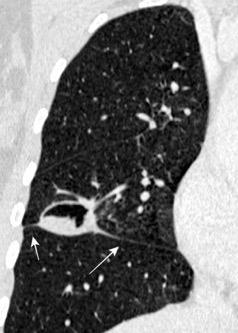

33. ENF. TORACOABDOMINAL. SEUDOQUISTE PANCREÁTICO

3 rasgos: Conexión entre mediastino y lesión pancreática. Derrame pleural Hallazgos de pancreatitis. Matsusue E et al.Three cases of mediastinal pancreatic pseudocysts. Acta Radiol Open. 2016 .